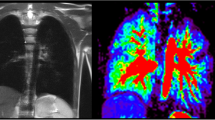

Current structural MRI shows a slightly hyperinflated middle lobe, which has expanded to the right lower posterior thorax. In this area, functional MRI shows locally reduced fractional ventilation and a large local decrease of perfusion, which leads to an increased overall QDP (Fig. 1). Overall (global) fractional VDP, however, is normal. Body plethysmography and spirometry (Table 1) are normal, excluding a severe restriction, obstruction or hyperinflation. The lung clearance index is above the norm, indicating inhomogeneity of ventilation.

A 7-year-old girl following lobectomy of the right lower lobe for hybrid lesion (intralobar bronchopulmonary sequestration, CPAM type 1) and an increased lung clearance index of 8.37 turnovers. a A sagittal T2-weighted image (repetition time [TR]/echo time [TE] 3.3/1.3 ms) and (b) a coronal T1/2-weighted image (TR/TE 1.5/07 ms) demonstrate expansion of the middle lobe into the cavity of the resected right lower lobe. c-f Coronal functional magnetic resonance imaging maps: (c) coronal fractional ventilation, (d) fractional ventilation defect percentage (brighter blue areas represent reduced function), (e) relative perfusion and (f) relative perfusion defect maps (brighter orange areas represent reduced function) show a fractional ventilation defect percentage (13.1%) within the norm and an increased perfusion defect percentage (26.1%) in the area of the former right lower lobe, to which region the middle lobe has expanded (e) (white arrow). Yellow dashed lines indicate plane levels. White dashed line indicates lung fissure for better visibility. CPAM congenital pulmonary airway malformation